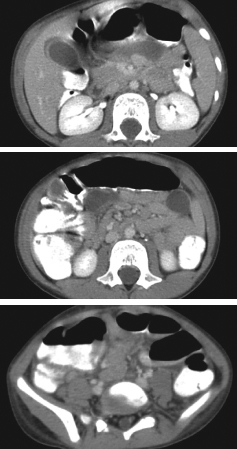

Tenecia Deans, MD; Stacy Higgins, MD

<p>For 4 days, a 62-year-old woman with type 2 diabetes mellitus had constant, severe, crampy abdominal pain associated with nausea, non-bloody emesis, and anorexia, but not fever. She reported that...